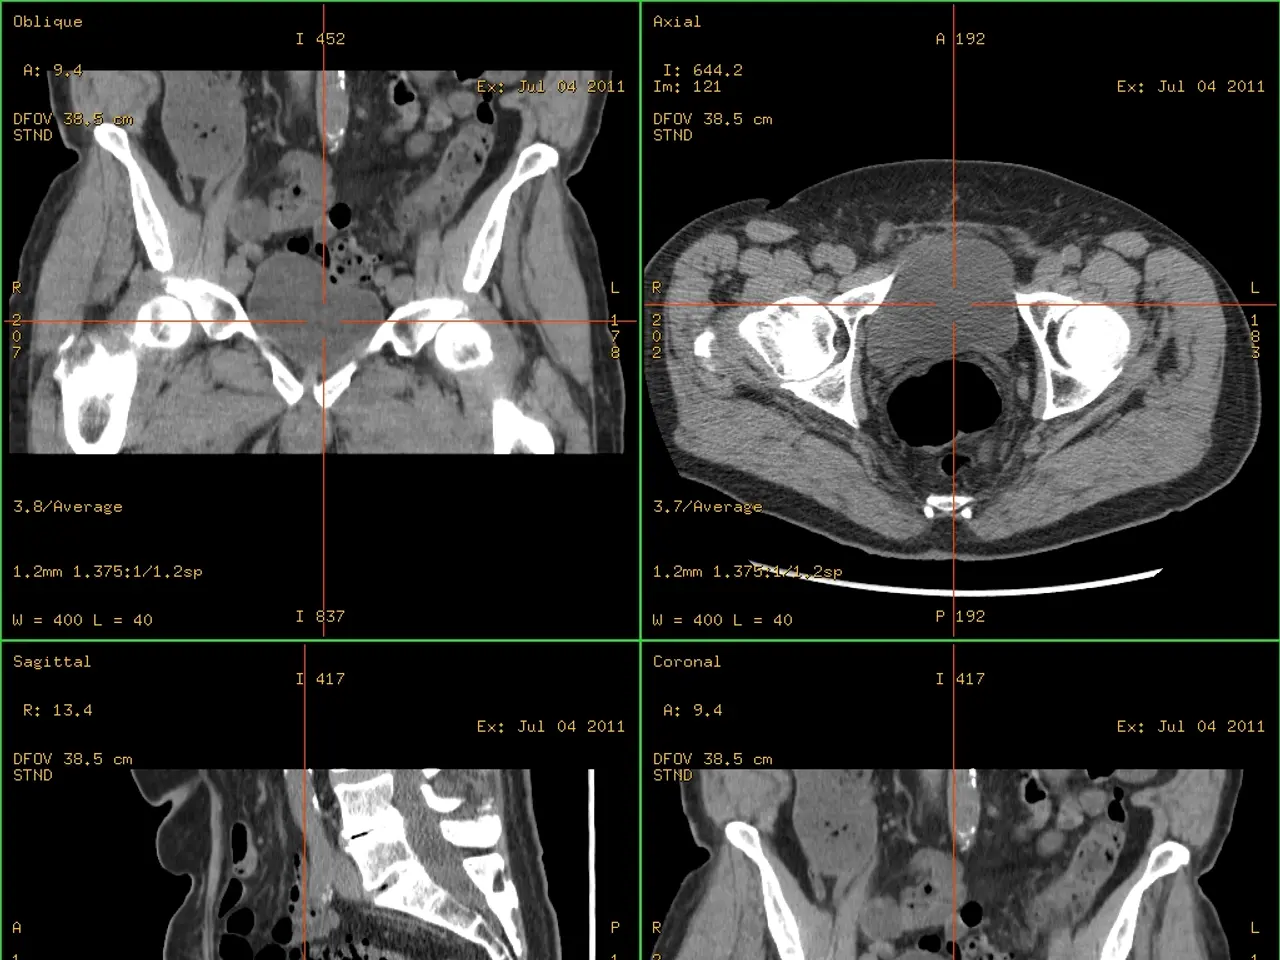

The image shows a CT scan of a patient's abdomen with a green background. The scan is displayed on a computer screen, providing detailed information about the patient's anatomy.